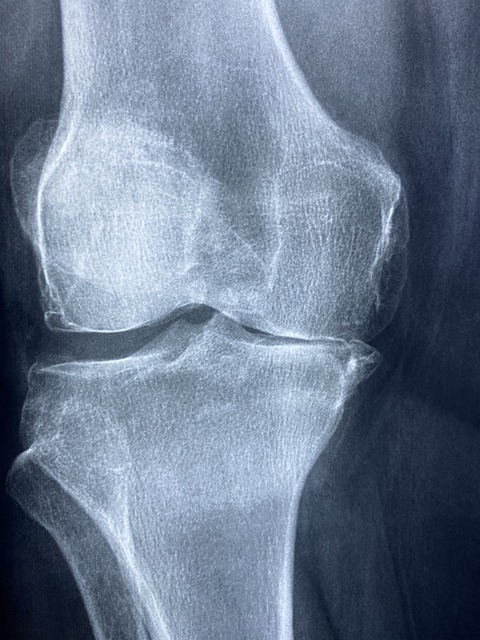

퇴행성 관절염은 관절 연골이 점진적으로 손상되어 발생하는 가장 흔한 관절 질환입니다. 주로 나이가 들면서 관절 사용으로 인한 마모와 퇴행성 변화로 인해 발생합니다. 이 질환은 주로 무릎, 엉덩이, 손가락, 그리고 척추와 같은 부위에서 많이 나타납니다.

퇴행성 관절염의 주요 위험 요인

- 나이: 나이가 들수록 관절 연골이 손상되기 쉽습니다. 대부분의 환자는 중년 이후에 증상이 나타나며, 60세 이상에서 많이 발생합니다.

- 비만: 과체중은 관절에 가해지는 부담을 증가시킵니다. 특히 무릎 관절에 큰 영향을 미치며, 체중 감량은 증상 완화에 큰 도움이 됩니다.

- 관절 손상 병력: 과거 관절 부상 경험이 있는 경우 퇴행성 변화가 더 빨리 진행될 수 있습니다. 스포츠나 사고로 인한 관절 손상이 대표적 예입니다.

- 유전적 요인: 가족력이 있는 경우 발병 위험이 높습니다. 유전적 소인이 있는 사람은 퇴행성 관절염에 걸릴 확률이 높습니다.

치료법으로는 약물 치료, 운동 요법, 체중 감량, 관절 주사 등이 있습니다. 약물 치료는 통증 완화와 염증 감소를 목표로 하며, 운동 요법은 근육 강화와 관절의 유연성을 유지하는 데 도움이 됩니다. 체중 감량은 관절에 가해지는 부담을 줄여 증상을 완화시킬 수 있습니다.

관절 주사는 고농도의 히알루론산이나 스테로이드 주사로, 때때로 단기적인 통증 완화에 효과적입니다. 심한 경우 수술적 치료도 고려됩니다. 관절 치환술이나 관절경 수술이 대표적인 수술 방법입니다. 퇴행성 관절염은 완치가 어려우나, 적절한 치료와 관리로 증상을 완화하고 삶의 질을 높일 수 있습니다. 규칙적인 운동과 올바른 생활 습관이 중요합니다.